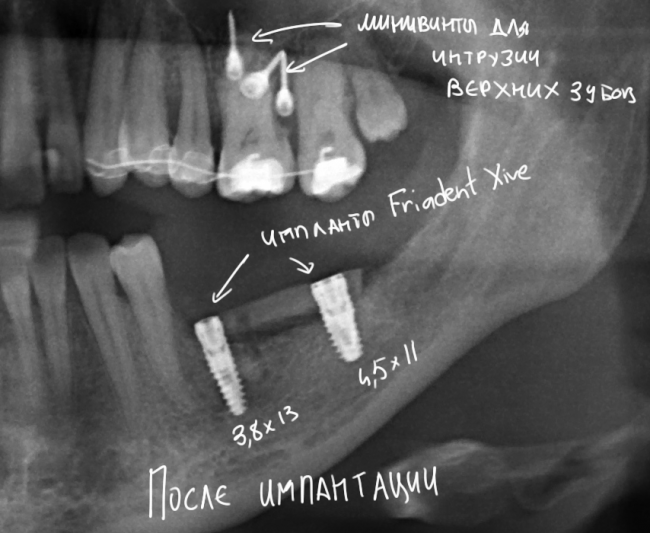

И вот ситуация конечная, уже с имплантами. С начала лечения прошло три месяца.

И с обозначениями:

«Пустое пространство» под блоком мы заполнили аутокостной стружкой, а сверху закрыли барьерной мембраной BioGide. Самое сложное в данной работе было, на мой взгляд, подогнать размер блока, «собрать» слизистую оболочку и наложить швы так, чтобы пациентка не кусала послеоперационную рану верхними зубами. Кстати, как видите, на верхние зубы уже наклеили брекеты — начали ортодонтическое лечение.

В данной работе я использовал импланты Friadent Xive. Это наш с пациенткой выбор.

Снимок после проведенной имплантации:

Винты, фиксировавшие блок, удалены. Имплантаты позиционированы по разметке ортопеда, исходя из планируемой ортопедической конструкции.

Многих пациентов также интересует, как заживает тот участок челюсти, с которого был взят костный блок для пересадки. На снимке выше очень хорошо видно, что через три месяца костная ткань там почти полностью восстановилась — область забора блока еле видна.

Вот схема:

На верхней челюсти — микровинты в качестве кортикальной опоры, необходимой для интрузии зубов. Поскольку костная ткань верхней челюсти не очень плотная, и винты, как оказалось, не дают нужной поддержки, в дальнейшем планируем заменить их на микропластину.